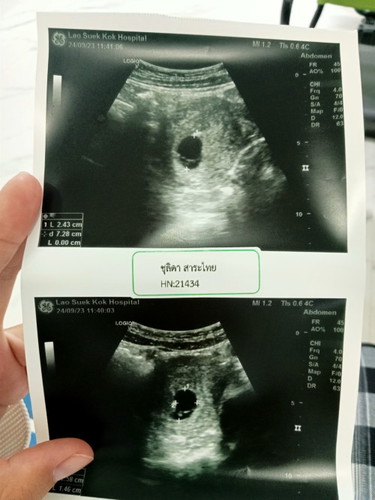

อัลตร้าซาวด์ท้องแรก

10สัปดาห์3วัน ไปอัลตร้าซาวด์วันนี้ยังไม่เจอตัวน้องเลยคะ รู้สึกเป็นกังวลมาก แม่ๆคนไหนมีคำแนะนำไหมค่ะยังไม่โอกาศเจอน้องไหม#ฟีด

เรา 9 w 6 d ไปซาวน์ทางช่องคลอดเมื่อวานค่ะ น้องเหมือนในรูปเลย คุณหมอบอกว่าน้อง 3 มิล ที่จริงต้อง 3 ซม ซึ่งรออีก 3 สัปดาห์ไปพบหมออีกครั้ง เราร้องไห้ตั้งแต่ห้องคุณหมอเลย ท้องแรกค่ะ ก็ได้แต่ภาวนาขอให้น้องเติบโตแข็งแรง เรายังรอน้องค่ะ

คุณแม่ซาวด์ยังไงค่ะ บ้านนี้9w ซาวด์ผ่านหน้าท้องไม่เจอค่ะ คุณหมอเลยซาวด์ผ่านช่องคลอด เจอค่ะ ได้ยินเสียงหัวใจน้องด้วยนะคะ

ซาวผ่านหน้าท้องคะ คุณหมอนัดอีกที2ตุลาคม